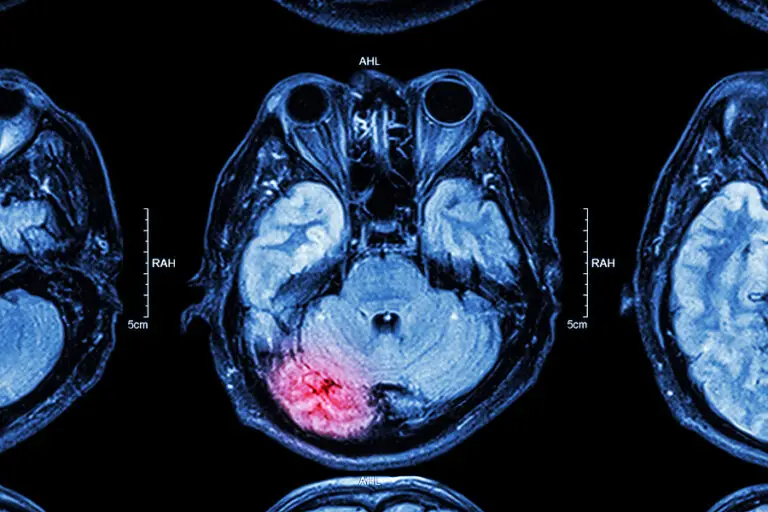

A new study says the position that a person plays in sports like football or hockey won’t affect the risk of concussion-related brain disease later in life. According to a HealthDay report, the number of